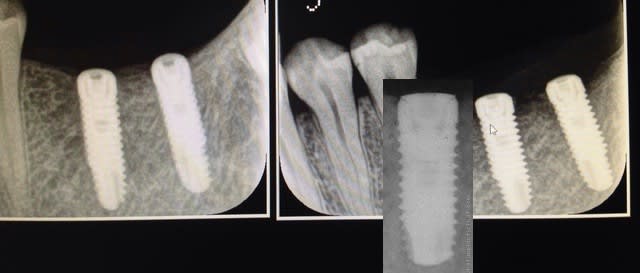

A 3 semaines, je revois le patient et fait une radio, il y a une perte osseuse autour des cols et la gencive un peu boursoufflée cloquée avec un peu de pus qui sort. Je décide de remettre le patient sous Antibio (augmentin), une semaine après, ça semble mieux mais je prolonge encore l'antibio.

Ci jointes radio post op et à 3 semaines et dernière photo de gencive.

j'aime pas non plus la deuxième radio avec le liseret le long des 2 implants...

les clichés sont pas très comparables, car l'angulation n'est pas la même, donc, pas si sur qu'il y ai perte osseuse: peut etre posé pas assez enfouis...